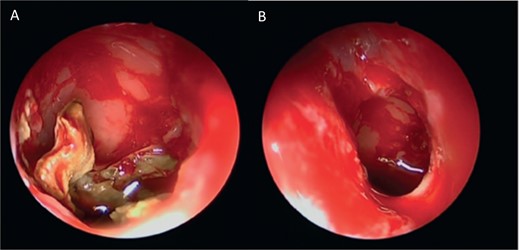

Intra-operative endoscopic view (A) right middle meatal antrostomy showing fungal debris, (B) clean right maxillary sinus after removal of the debris.